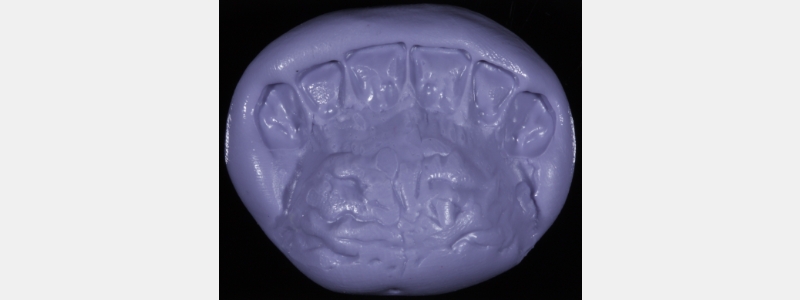

I use the indirect-direct approach, whereby a diagnostic mock-up is fabricated indirectly. Then, a stent is made of the mock-up both facially and palatally using a clear PVS (e.g., Memosil [Kulzer], RSVP [Cosmedent], or Exaclear [GC]). The stent is filled with flowable composite and seated in the patient’s mouth (it’s essential not to apply any bond). The resin is polymerized, and the stent is removed. This allows you and the patient to visualize the result, a more powerful communication tool than a diagnostic wax-up.

A clear PVS stent was fabricated from a digital wax-up and filled with flowable composite (Fig. 24).

I prefer an opaque flowable composite for this application because a regular flowable composite tends to be quite translucent, making the underlying tooth structure visible, which distracts many patients. The flowable composite was polymerized, and the stent was removed.